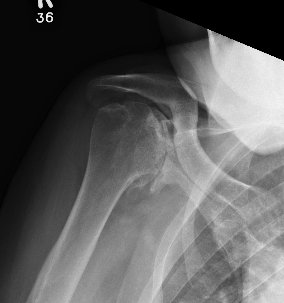

Levigne and Franceschi Classification

Three main patterns

| Type 1 | Type 2 | Type 3 |

|---|---|---|

|

Upward migration Superior glenoid wear |

Concentric medial migration Deficient medial bone stock |

Destructive |

Due to rotator cuff insufficiency Most common pattern |

||

Rheumatoid arthritis with superior and medial wear